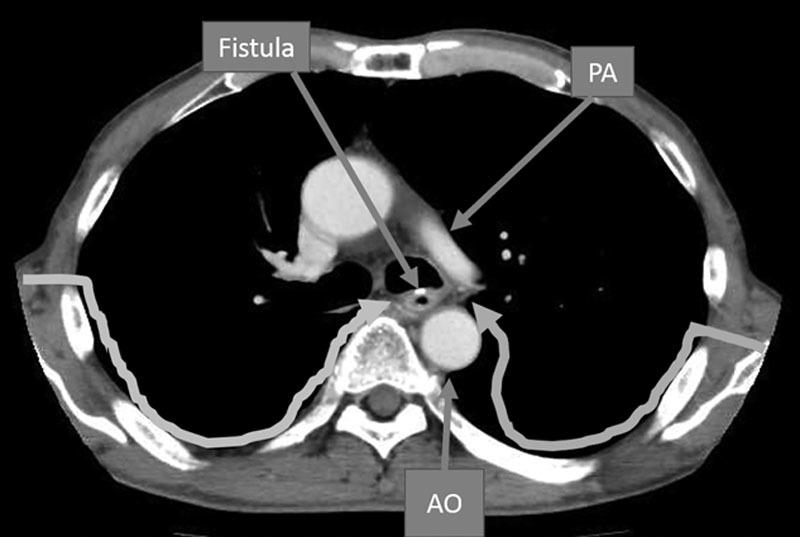

A postoperative aerodigestive fistula is one of the rare but critical complications after esophagectomy, and management is challenging. The essential keys to successful treatment of these fistula are thorough debridement and complete closure followed by separation of the respiratory and digestive tract. We present a case of a recurrent bronchoesophageal fistula between the left main bronchus and neo esophagus, which was successfully treated through a contralateral approach. The fistula was debrided and closed primarily through a right thoracotomy, and the interposition of a pedicled latissimus dorsi musculocutaneous flap from the right side was carried out. The patient was able to resume oral feeding at 16th postoperative day.

https://cdn.ncbi.nlm.nih.gov/pmc/blobs/a29b/5640357/7666d020012a/gox-5-e1484-g001.jpg